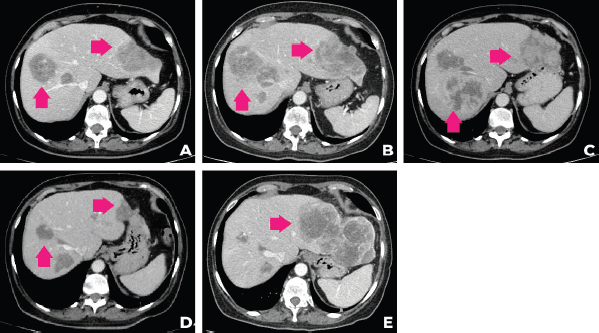

In September 2021, after 3 months of talazoparib, clinical improvement of abdominal pain and liver partial response was observed. Tumour response was ongoing at the time of this case submission (December 2021). A summary of the patient’s main radiologic findings is portrayed in Figure 2 and a timeline of patient evolution in Figure 3.

Figure 2. Evolution of the patient’s computer tomography scans in different time periods. (a): CT of December 2020, (b): April 2021, (c): June 2021, (d): September 2021, (e):December 2021.